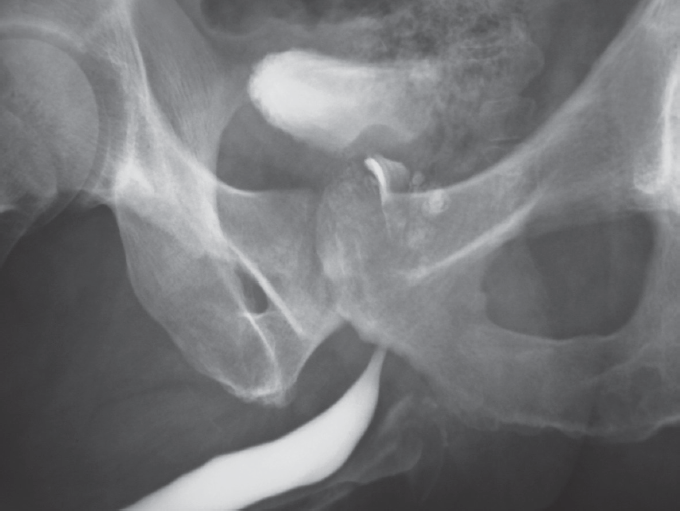

Ультразвуковое исследование почек: без патологических изменений. Трансректальное ультразвуковое исследование предстательной железы: объем железы увеличен до 54 мл, эхоструктура неоднородна, определяется несколько полостей до 3 см в диаметре. Видеофиброуретроскопия: семенной бугорок отечен, визуализируются несколько гнойников (рис. 2).

Рис. 2. Уретроскопия пациента с туберкулезом простаты (фото Н.В. Федоренко)